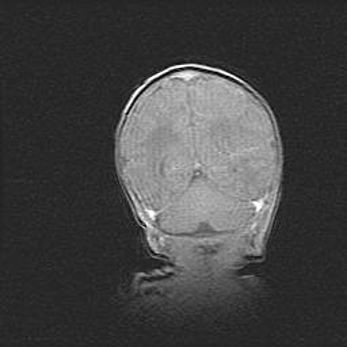

Открытая гидроцефалия.

Возраст: 9 месяцев 12 дней

Вес: 6800 г

Пол: мужской

Окружность головы: 41,5 см

Срок гестации: 28 недель

Гидроцефалия головного мозга у новорожденных имеет характерный признак: опережающий рост окружности головы приводит к визуально хорошо определяемой гидроцефальной форме сильно увеличенного в объёме черепа. Детские неврологи определяют следующие симптомы гидроцефалии у грудничков: выбухающий напряжённый родничок, частое запрокидывание головы, смещение глазных яблок к низу.